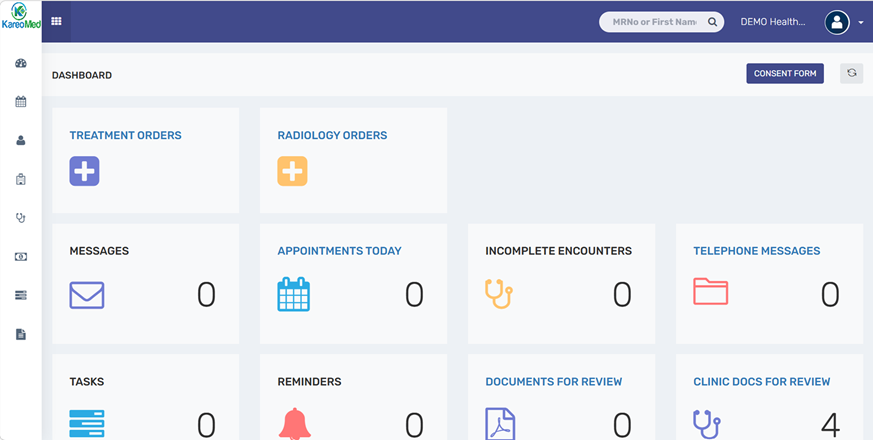

One platform to manage your complete EMR workflow

Built for modern healthcare—secure, reliable, and

ready for ADHICS, Shafafiya, Malaffi, and NABIDH.

Complete EMR

for Clinics & Homecare

for Clinics & Homecare

A unified EMR platform for clinics and homecare providers to manage patient records, appointments, billing, care plans, and daily operations with ease.

Clinics/School Clinics

-

Registration

-

Appointments

-

Electronic Medical Records

-

Physician Note, Nursing Note

-

Clinical Coding

-

eClaim Management

-

ADHICS Compliance, Malaffi & NABIDH Integration